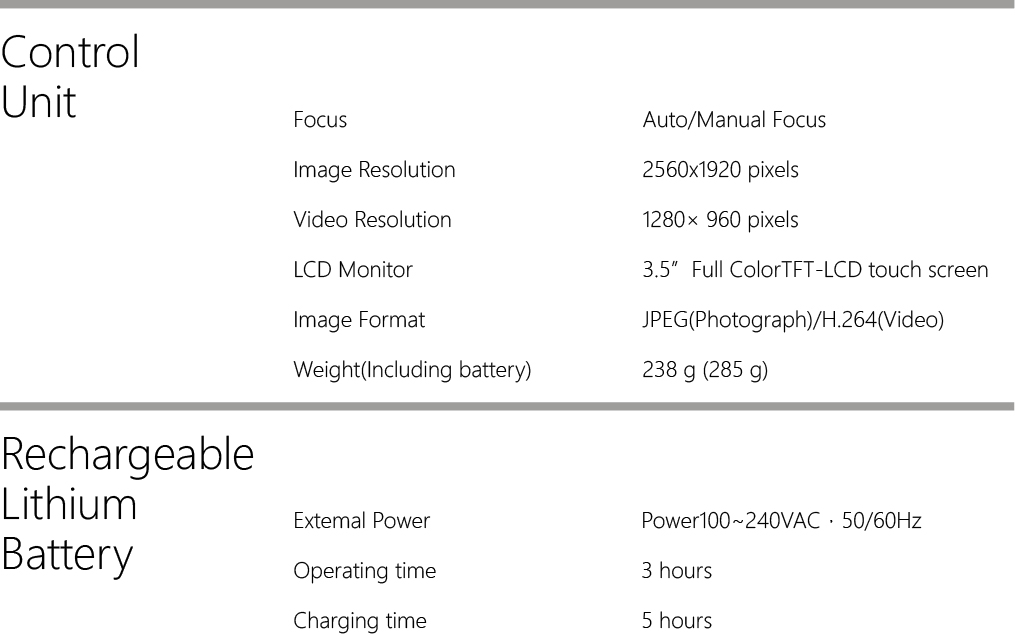

Technical Specifications